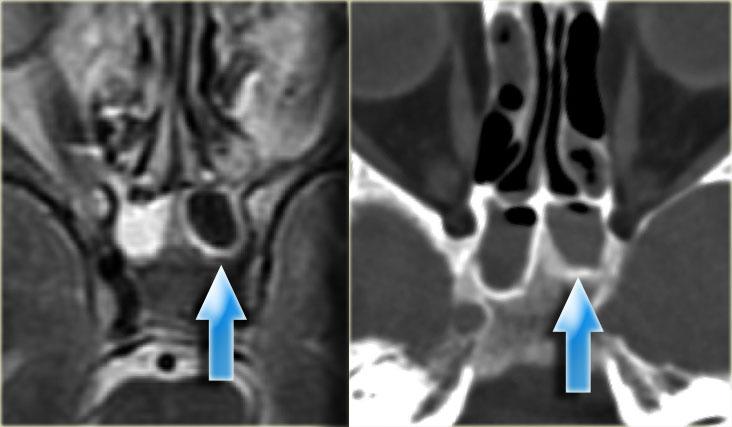

Ca bệnh minh họa này thể hiện rõ nét hình ảnh nang nhầy hai bên.

Bệnh nhân này có viêm xoang mạn tính với mờ đục toàn bộ xoang mũi, ứ đọng dịch nhầy trong các xoang hàm và nang nhầy hai bên kích thước lớn.

CT cho thấy tăng tỷ trọng và MRI cho thấy tăng tín hiệu trên chuỗi xung T2W – cả hai đều là dấu hiệu lành tính trong bệnh lý mũi xoang, gợi ý chất dịch giàu protein.

Có hình ảnh tái cấu trúc xương trơn láng và đẩy lồi thành xoang trán; mặc dù trông như có phá hủy xương tại ranh giới hốc mắt của xoang trán, nhưng thông thường phẫu thuật viên vẫn có thể quan sát thấy một lớp xương mỏng còn nguyên vẹn tại chỗ.